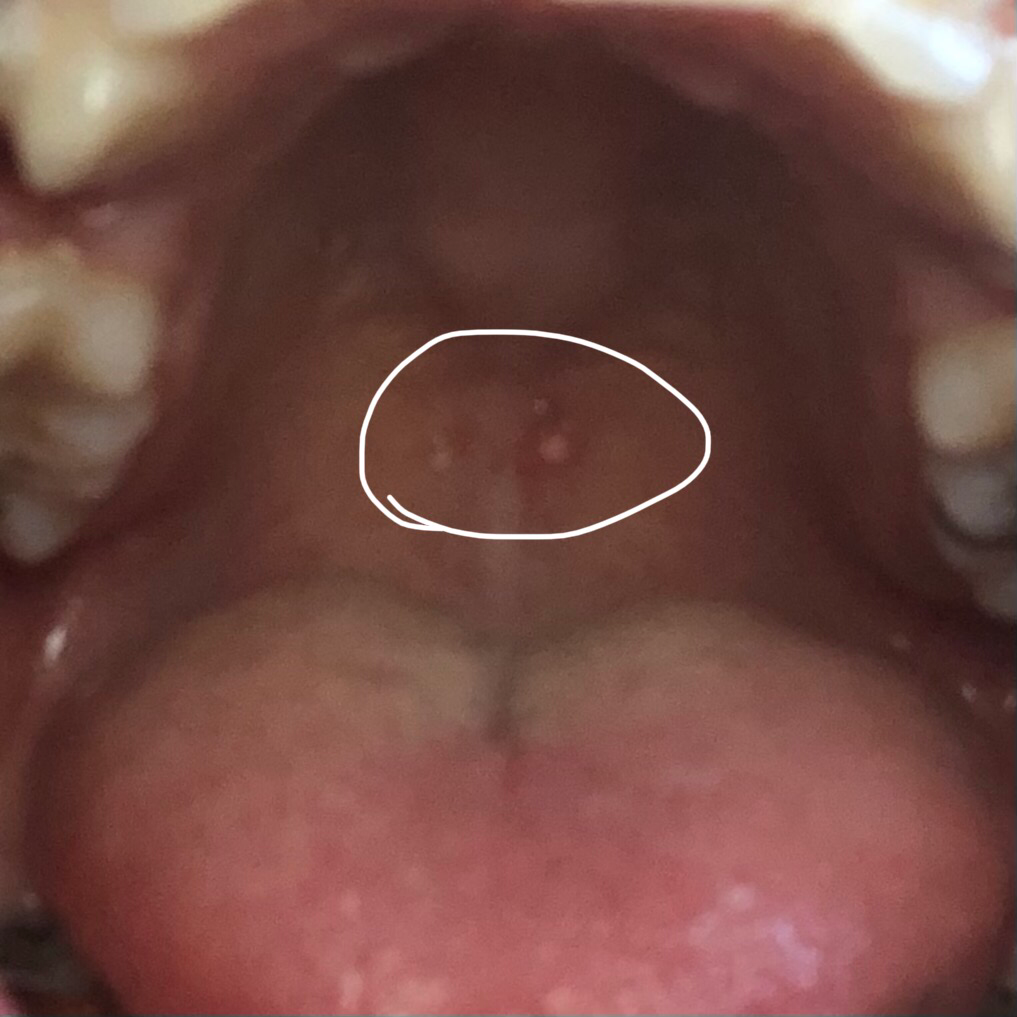

자고 일어나니까 목구멍쪽에 물집이 생겼어요

어제까지만 해도 없었는데 오늘 자고 일어나니까 생겼네요

어제 위내시경 하고 역류성식도염 약을 처방받아서 먹고 있는데요 약 먹은 지 하루도 안 됐는데 생겼네요 아프진 않고 그냥 물집이 거슬려요

약 때문에 생긴 건가요?

아니면 위내시경 하면서 목구멍이 자극 받아서 생긴 걸까요?

아니면 그냥 역류성식도염 때문에 물집이 생긴 건가요?

• 1번 째 사진

어제 위내시경을 받으셨다면 직, 간접적으로 구내염 발생에 영향을 주었을 수 있겠습니다. 비타민 잘 챙겨드시고 며칠 쉬어보시면 될 것으로 보입니다. 해당 병변이 점점 더 악화된다면 병원을 방문하시기 바랍니다.